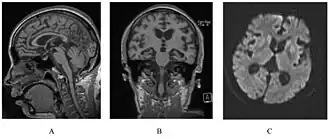

![]() У человека с наследственным прионным заболеванием наблюдается атрофия мозжечка. Это очень типично для синдрома ГШШ | |

Синдром встречается у лиц в 40-50 лет и характеризуется, главным образом, мозжечковой атаксией, расстройствами глотания и фонации, прогрессирующей деменцией на протяжении от 6 до 10 лет (средняя продолжительность болезни составляет 59,5 месяцев), после чего наступает смерть. Инкубационный период длится от 5 до 30 лет.

Морфологические изменения при этом синдроме аналогичны обычным трансмиссивным подострым спонгиоформным энцефалопатиям. Отличительной его чертой является наличие большого количества концентрических амилоидных пластин, которые выявляются чаще в молекулярном слое коры мозжечка, но также их можно обнаружить и в коре мозга. Иммунопозитивные бляшки могут быть величиной от 150 до 500 микрон в диаметре. Они слабо PAS-положительны и редко показывают зелёное двойное лучепреломление при окрашивании конго красным. Сходство с болезнью Альцгеймера заключается в наличии нейрофибриллярных структур в цитоплазме нейронов. Отличительной чертой является то, что главный белковый компонент амилоидных ядер — это прионный белок PrP, а не AB-пептид.